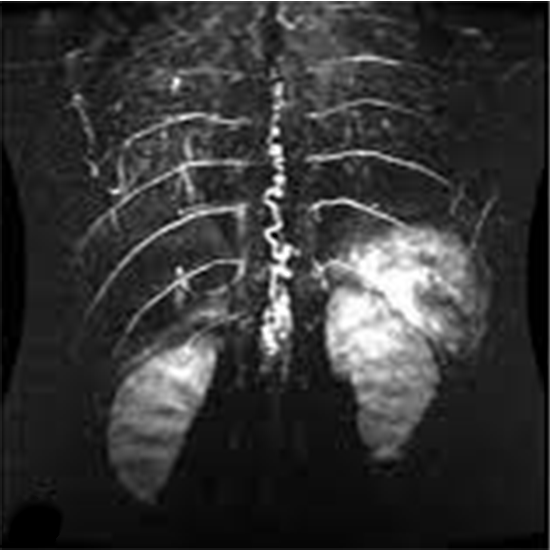

Spinal angiography is a detailed look at how blood flows into and out of the spinal cord, vertebrae, and soft tissue around it.

MRA (Magnetic Resonance Angiography) spine is a non-invasive medical diagnostic tool used to obtain detailed images of the spine and the related tissue in the spine. MR angiography (MRA) of the spinal is used to show abnormalities like fractures, injuries, infections, inflammations etc. in the lumbar spine.